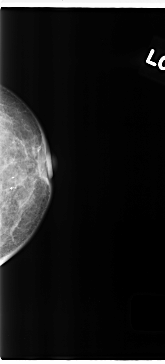

C_0221_1.LEFT_CC

LEFT_CC LINES 4728 PIXELS_PER_LINE 2136 BITS_PER_PIXEL 12 RESOLUTION 50 NON_OVERLAY